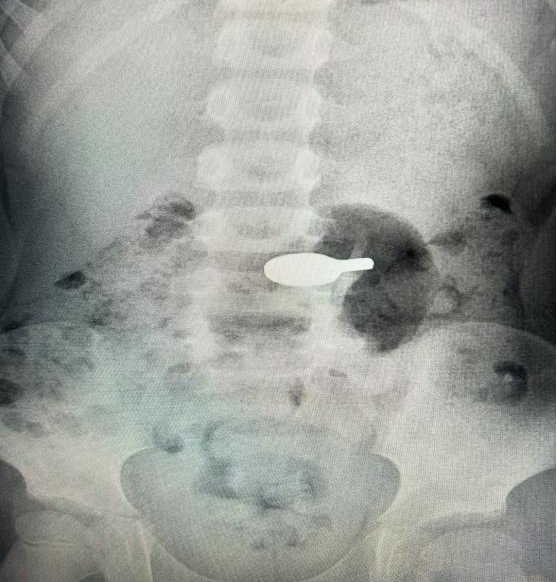

据家长描述,乐乐在与同伴玩耍时,将一枚乒乓球拍样的磁铁玩具放入口中,不慎吞下。不久后,孩子开始出现腹部隐痛,特别是腹部靠近铁桌子时更明显,家长察觉异常后立即带至我院就诊。影像学检查发现一乒乓球拍样异物。

经消化内科医师评估,征得乐乐家属知情同意后,在麻醉医学科配合下,消化内镜中心急诊团队紧急出诊,胃镜下找到异物并精准夹取,仅用数分钟便将磁铁完整取出,过程顺利。术后乐乐腹痛明显缓解,出院时还说记住这次教训了,以后再也不敢把玩具放进嘴巴了。